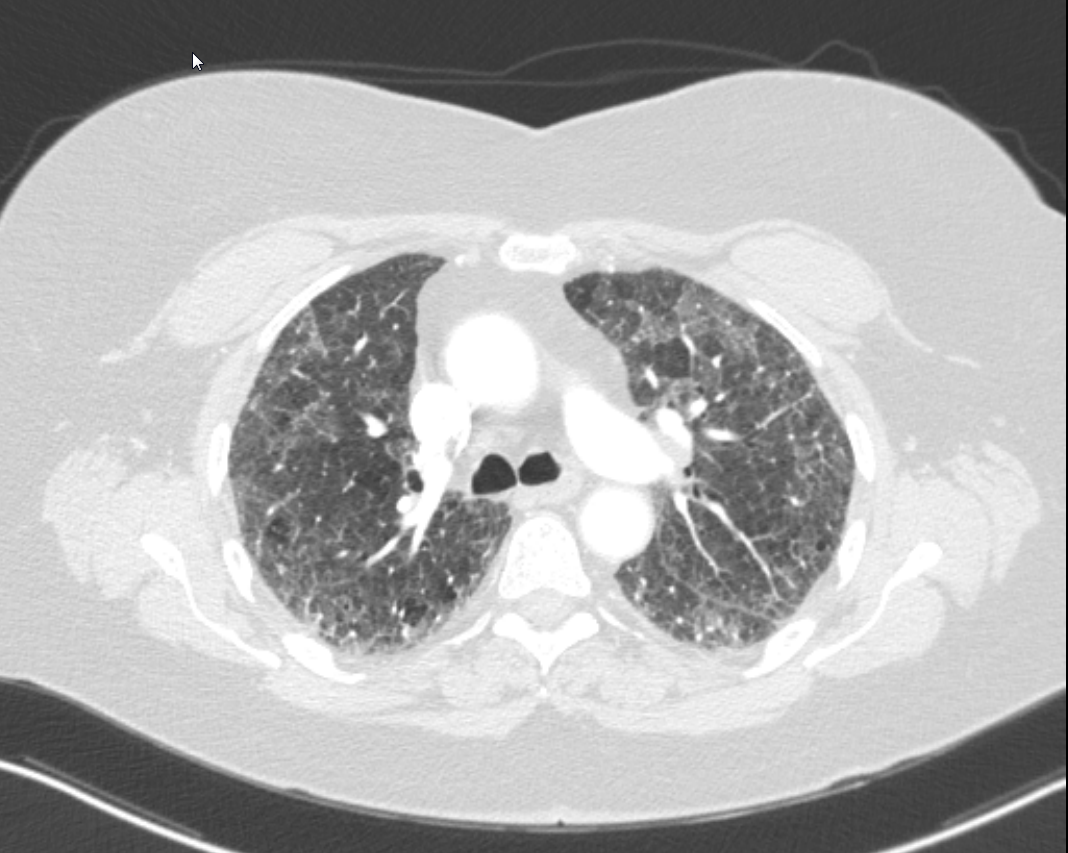

Case Presentation: 64-year-old female is admitted for workup and management of subacute, progressive dyspnea, pleuritic chest pain, dry cough, and new oxygen requirement. History is significant for plaque psoriasis on adalimumab (initiated 3 months prior to presentation), ulcerative colitis status post proctocolectomy, sicca symptoms, Raynaud’s phenomenon, GERD, maternal history of rheumatoid arthritis, and a 50-pack-year smoking history. CT showed moderate, multifocal GGOs consistent with nonspecific interstitial pneumonia (NSIP) or usual interstitial pneumonia (UIP) without honeycombing. Pulmonary function testing showed severely reduced DLCO. Ejection fraction was 60% without significant echocardiographic abnormalities. Labs remarkable for normal leukocyte count; moderately elevated ESR and CRP; and mildly elevated RNP, LDH, and aldolase. Rheumatologic and infectious testing (including bronchoalveolar lavage) was otherwise negative. Transbronchial biopsy showed bronchiolar wall and parenchyma without neoplasm or granuloma. Video capillaroscopy confirmed secondary Raynaud’s. Adalimumab was stopped, and she was started on prednisone 30 mg daily. She improved clinically and was discharged with home oxygen and plans for outpatient rheumatology and pulmonology follow up. Repeat CT chest one month later showed significant improvement in GGOs but persistence of fibrotic ILD. Pulmonology believed the remaining disease represented UIP versus NSIP related to underlying connective tissue disease. Rheumatology felt that the ILD with elevated RNP in the setting of her other rheumatologic symptoms were suggestive of mixed connective tissue disease (MCTD). Azathioprine was started with plans to wean the prednisone. She has since been improving clinically.